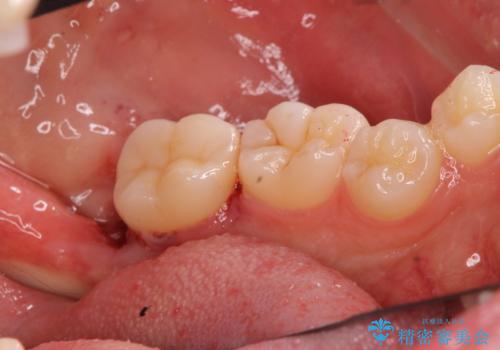

適合の良い詰め物が入りました。

親知らずは虫歯になるリスクが高いため抜歯をする事をお勧めします。